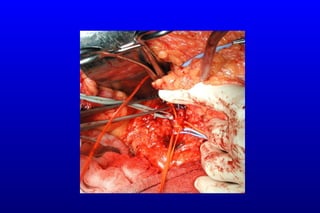

Cerrahi embolektomi ± rezeksiyon

Non viable dokuların rezeksiyonu + anastomoz / stoma